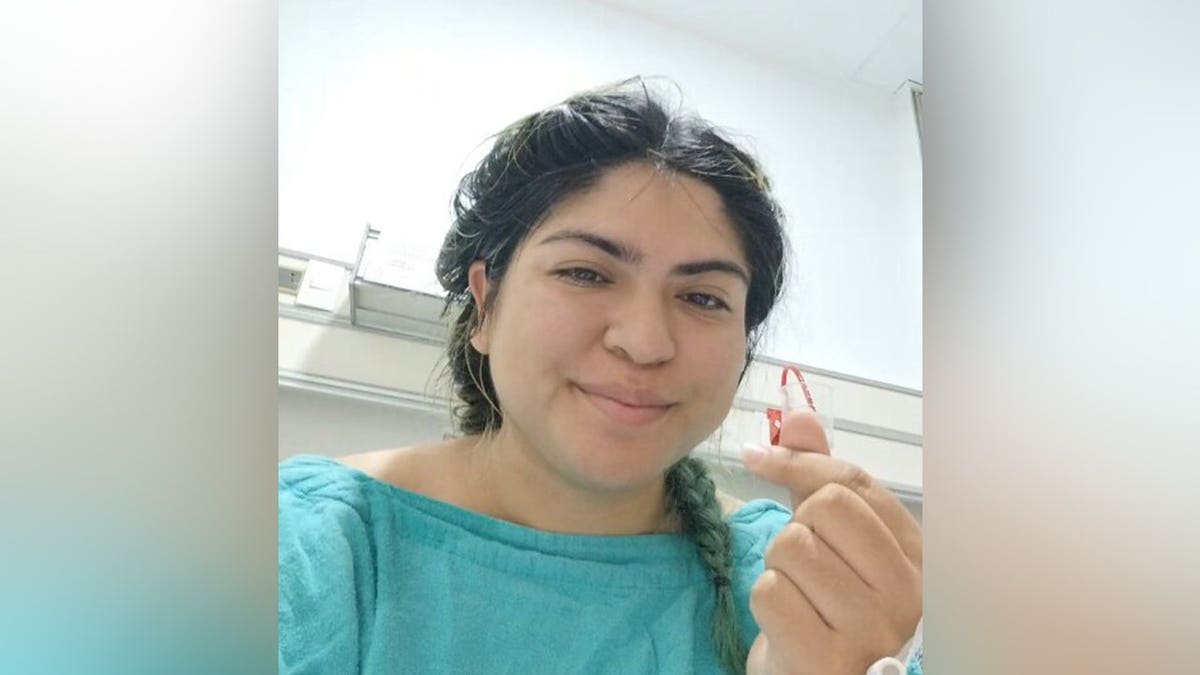

What was supposed to be a routine 20-minute extraction turned into a high-stakes medical procedure. (Jam Press)

What was supposed to be a routine 20-minute extraction turned into a high-stakes medical procedure. During the initial attempt, surgeons were unable to budge the object because it had already begun attaching to her internal tissue.

“It ended up taking an hour and 20 minutes, and they still couldn’t remove it because it was attached to my body,” she said, according to the Jam Press report.

Facing a second, more invasive surgery and the risk of a fatal hemorrhage, Deyanira prepared for the worst. The night before the surgery, she wrote a farewell letter to her loved ones.

“I was honestly thinking, ‘I’m going to die,'” she said. “It’s a horror I wouldn’t wish on anyone.”

The woman’s surgeon was equally stunned by how close the metal was to her heart. According to Deyanira, the doctor told her, “It seems God takes care of his creatures.”

If the metal had punctured her lung or heart before doctors discovered it, Deyanira said she likely would have died from a lung collapse or perforated aorta.